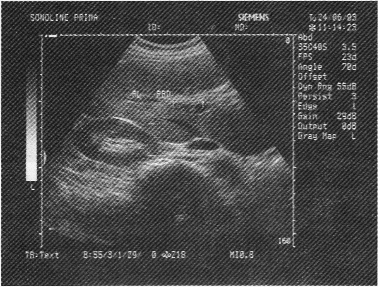

女性,30岁,反复发作性剧烈的右上腹痛,加重1天,超声检查如图所示,最可能的诊断是

• A.肝内胆管结石

• B.肝内胆管癌

• C.肝内胆管蛔虫

• D.肝内胆管积气

• E.胆管内引流管回声